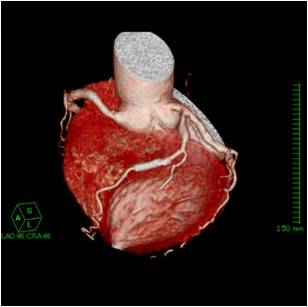

心筋梗塞や狭心症を引き起こす原因は、心臓周りを取り巻く血管(冠動脈といいます)の内部が狭くなったり閉塞したりして血液供給が不十分になり発生します。

X線CTでの心臓検査は、造影剤を腕から入れて、数秒間の撮影を行うだけで検査が終わりますので日帰り検査も可能であり、被ばくの心配等も少ないです。